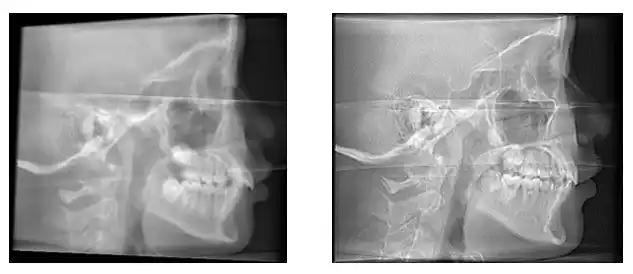

头颅侧位片可用于口腔正畸,正颌治疗前,中,后牙及颌骨相对位置的改变

正畸前后的头颅侧位片对比侧面轮廓上重要的关键点,在理想情况下,都会